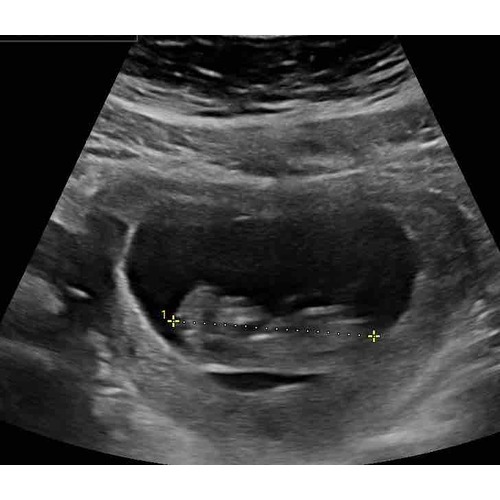

Als ik naar al mij 4 keer de zwangerschappen en echo's heb gekeken rond de 6 weken was het bij mij ook allemaal hobbelig en niet mooi rond. 1 van alle is esn miskraam geworden maar dat konden ze niet zien aan de vorm ik heb het ook echt nog nooit gehoord... de volgende echo's werden ze al wat mooier rond... maar hun hebben ervoor gestudeerd... wanneer mag je terug?

Hoi allen, hoe is het uiteindelijk bij jullie allemaal verlopen? Wij hadden gister onze eerste echo (ongeveer 6.3 wk) en onze Vk was ook wat voorzichtig met goed nieuws brengen door de vorm van de vruchtzak. Echter wel een hartslag; langzaam maar dit hoeft nog niets te betekenen met dit termijn.